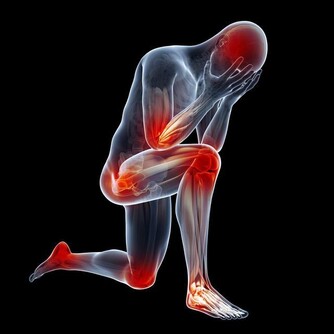

4、血管運動性鼻炎引起的鼻塞

血管運動性鼻炎這個名字聽上去很複雜,其實就是鼻腔內血管發炎。

雖然這種炎症的病因通常無從得知,不過壓力過大、甲狀腺功能異常、

香水和煙味的刺激以及減鼻充血劑的過度使用都會引起血管擴張,引發血管運動性鼻炎。